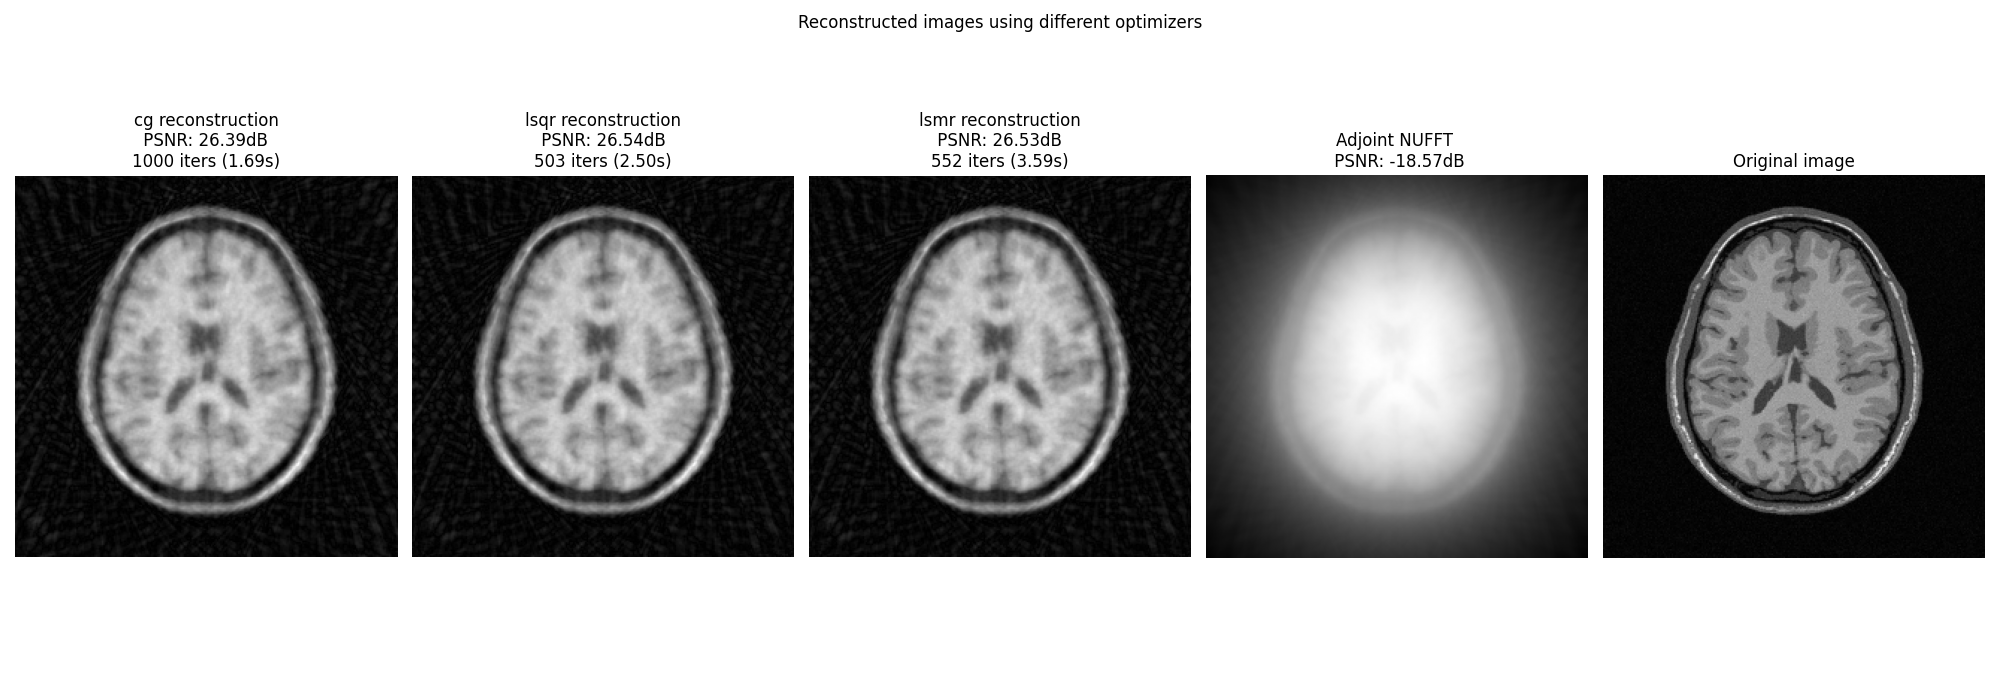

Display images#

fig, axs = plt.subplots(1, len(OPTIM) + 2, figsize=(20, 7))

for i, optim in enumerate(OPTIM):

axs[i].imshow(abs(images[optim]), cmap="gray", origin="lower")

axs[i].axis("off")

axs[i].set_title(

f"{optim} reconstruction\n PSNR: {iterations_cb[optim]['psnr'][-1]:.2f}dB \n"

f"{len(iterations_cb[optim]['time'])} iters ({iterations_cb[optim]['time'][-1]:.2f}s)"

)

axs[-1].imshow(abs(ground_truth), cmap="gray", origin="lower")

axs[-1].axis("off")

axs[-1].set_title("Original image")

axs[-2].imshow(

abs(adjoint),

cmap="gray",

origin="lower",

axs[-2].axis("off")

axs[-2].set_title(

f"Adjoint NUFFT \n PSNR: {psnr(abs(adjoint), abs(ground_truth), data_range=ground_truth.max()):.2f}dB"

fig.suptitle("Reconstructed images using different optimizers")

fig.tight_layout()

plt.show()